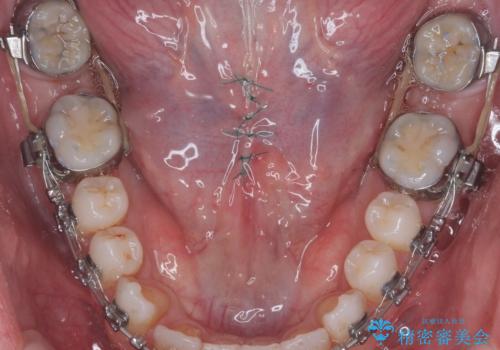

舌小帯の切除

- 他院で矯正治療をしているが、滑舌も気になるため舌小帯の切除を希望し来院されました。

手術自体は当日での処置が可能です。

抜糸は1週間から2週間の期間を置いた後治癒を確認してから行います。